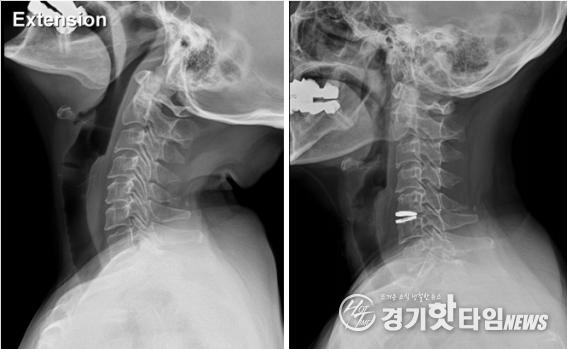

이러한 비수술 치료방법으로도 효과가 없다면 인공디스크와 같은 수술적 치료를 통해 치료를 고려해야 한다.